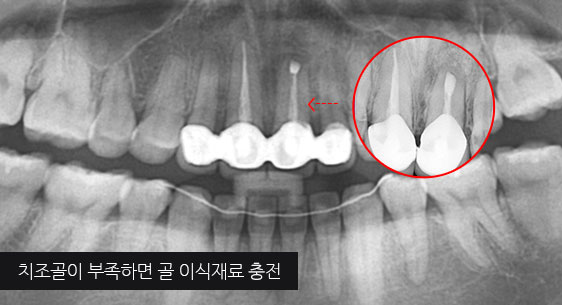

치조골이 절반만 남아있어도 치주치료를 통하여 자연치아를 살릴 수 있습니다. 타치과에서 임플란트 수술을 진단받은 경우에도

고운미소치과에서는 임플란트 수술을 안받고 치료가 가능하거나, 생각보다 훨씬 적은 수의 임플란트를 식립 하는 경우가 상당히 많습니다.

신경관이 막혀 있는 경우 재 신경치료로 낫지 않는 경우, 포스트가 있어 재 신경 치료를 할 수 없는 경우, 치아 뿌리까지 염증이 심하지만 이러한 염증을

제거 할 수 없는 경우, 고운미소 치과에서는 치조골 주위 염증조직을 제거하는 치근단절제술을 시행합니다.